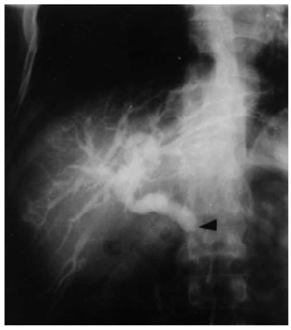

- ERCP - מראה תמונה של חסימה בדרכי המרה ובציטולוגיה הנלקחת על ידי מברשת ניתן לראות תאים ממאירים (תצלומים 51.8 ו- 52.8).